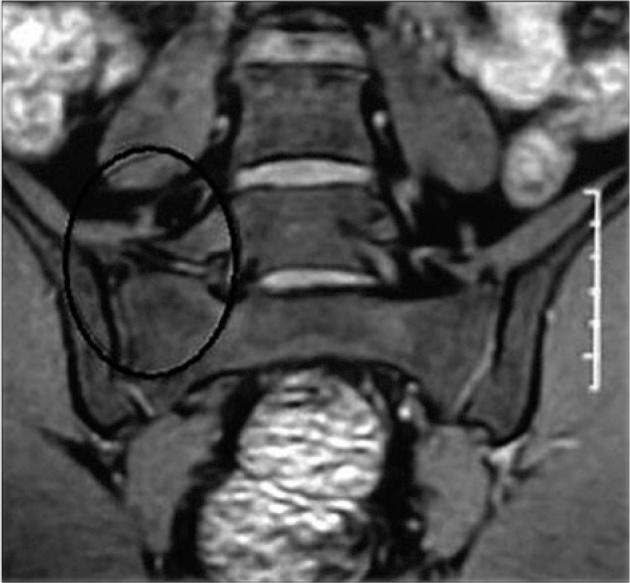

Increased stresses across the bony hemipelvis result when athletes with FAI attempt to achieve supraphysiologic, terminal ranges of motion (ROM) through the hip joint required for athletic competition. This can manifest as pain within the pubic joint (osteitis pubis), sacroiliac joint, and lumbosacral spine. Subclinical posterior hip instability may result when attempts to increase hip flexion and internal rotation are not compensated for by increased motion through the hemipelvis. Prominence of the anterior inferior iliac spine (AIIS) at the level of the acetabular rim can result in impingement of the anterior hip joint capsule or iliocapsularis muscle origin against the femoral head-neck junction, resulting in a distinct form of mechanical hip impingement (AIIS subspine impingement). Iliopsoas impingement (IPI) has also been described as an etiology for anterior hip pain. IPI results in a typical 3-o'clock labral tear as well as an inflamed capsule in close proximity to the overlying iliopsoas tendon. Injury in athletic pubalgia occurs during high-energy twisting activities in which abnormal hip ROM and resultant pelvic motion lead to shearing across the pubic symphysis.